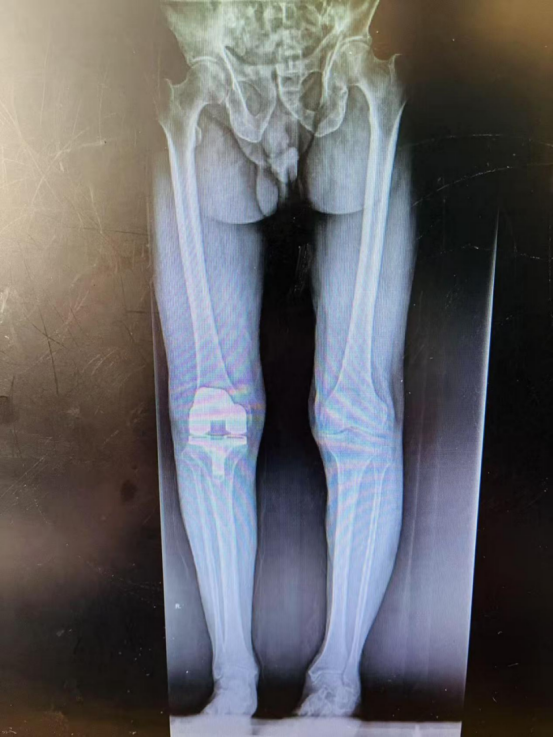

3月26日,富順縣人民醫(yī)院骨科中心成功為一名高齡患者行右側(cè)全膝關(guān)節(jié)置換術(shù),術(shù)后恢復(fù)良好,現(xiàn)已出院。

雖然患者87歲高齡,手術(shù)風(fēng)險較大,但之前行膝關(guān)節(jié)保守治療,效果不佳,嚴重影響生活,患者及家屬手術(shù)意愿強烈,在完善相關(guān)輔助檢查后,考慮無絕對手術(shù)禁忌,骨科團隊決定為其實施手術(shù)。3月26日,由骨一科主任楊勇主刀,王波主治醫(yī)師及廖銳主治醫(yī)師協(xié)助,麻醉科全力配合下完成右側(cè)全膝關(guān)節(jié)置換手術(shù),手術(shù)順利,術(shù)后患者逐步恢復(fù)出院,出院前已能下地扶拐行走。

全膝關(guān)節(jié)置換手術(shù)適合中重度膝關(guān)節(jié)炎保守治療無效的病人,屬于膝關(guān)節(jié)疾病終極治療方案,以往科室完成的膝關(guān)節(jié)置換手術(shù)多為60歲-80歲的患者,本次為87歲高齡患者行膝關(guān)節(jié)置換手術(shù),有賴于骨科團隊多年來深耕骨與關(guān)節(jié)疾病的底氣及近年來醫(yī)院的整體發(fā)展,同時也離不開患者對我們的信任。